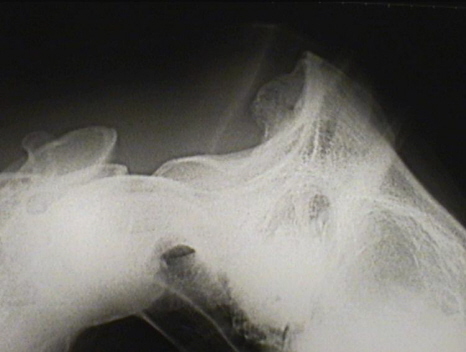

Insertionsdesmopathie Genick